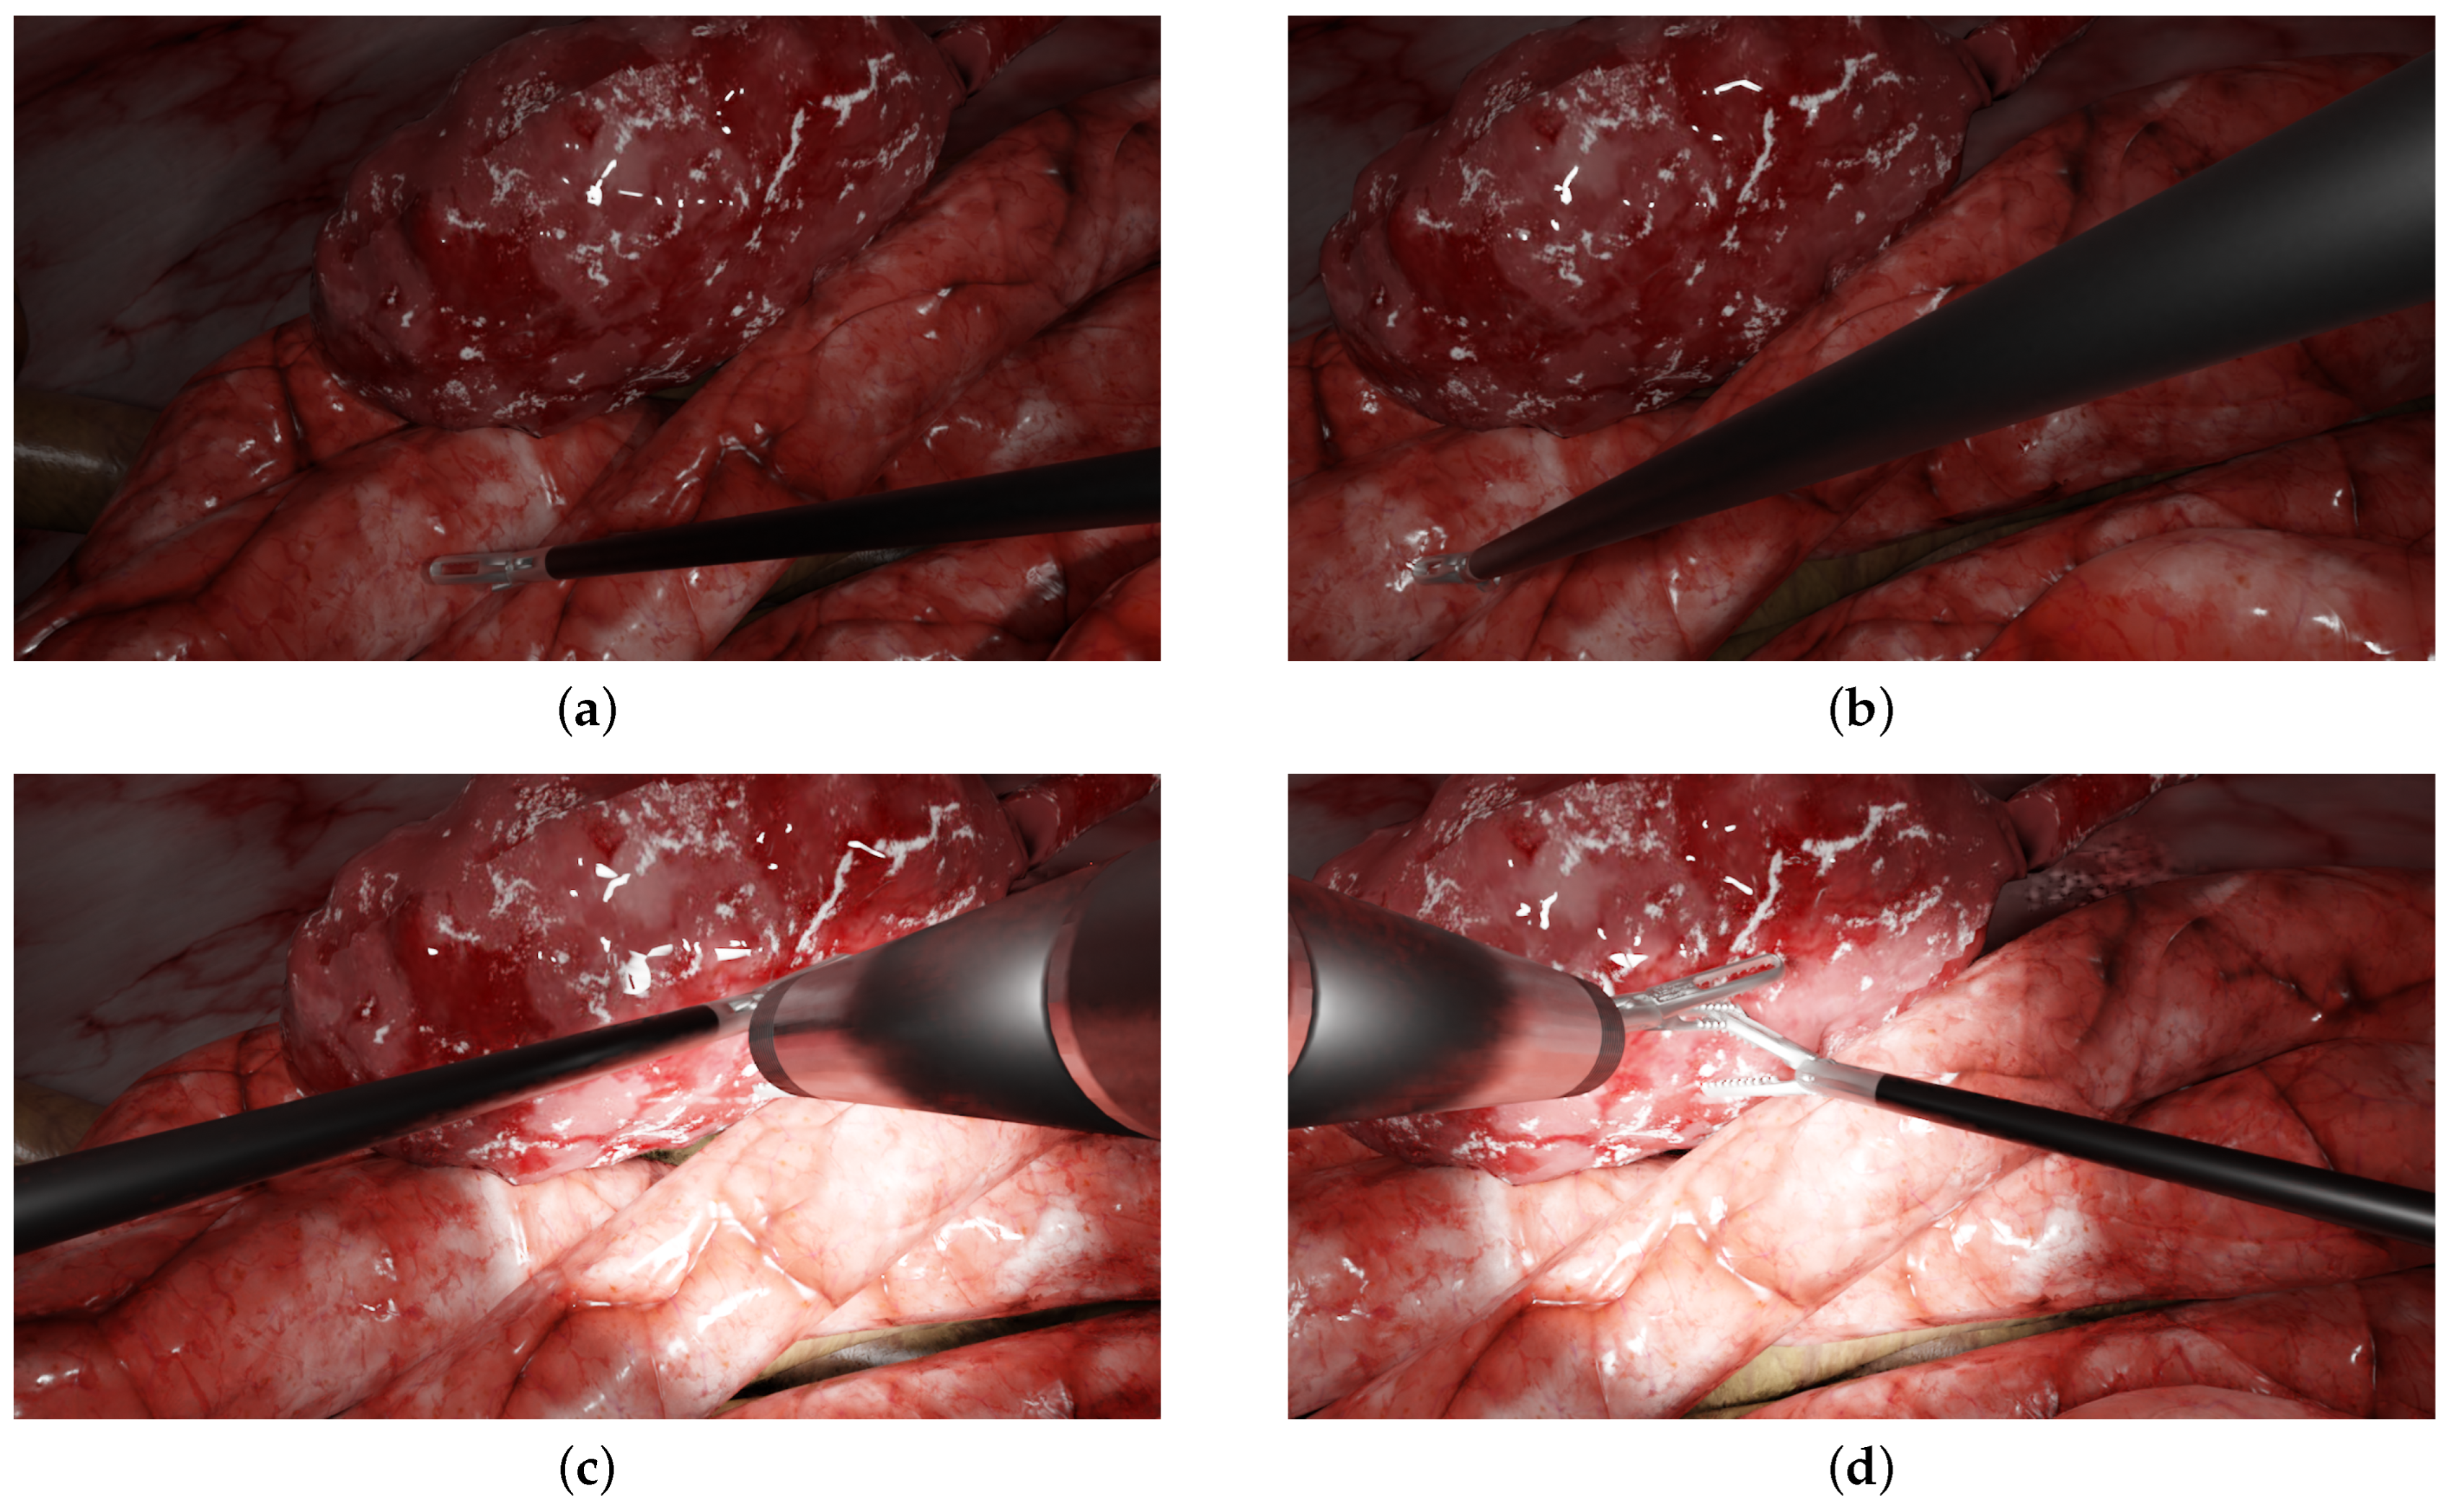

Figure 2.

Examples of typical laparoscopic situations: images from a multi-camera system rendered in the simulated environment. The left and right columns display the left and right simulated images of the prototype, respectively. (a,b) One forceps with no endoscope (c,d), two forceps, one endoscope and a halo.